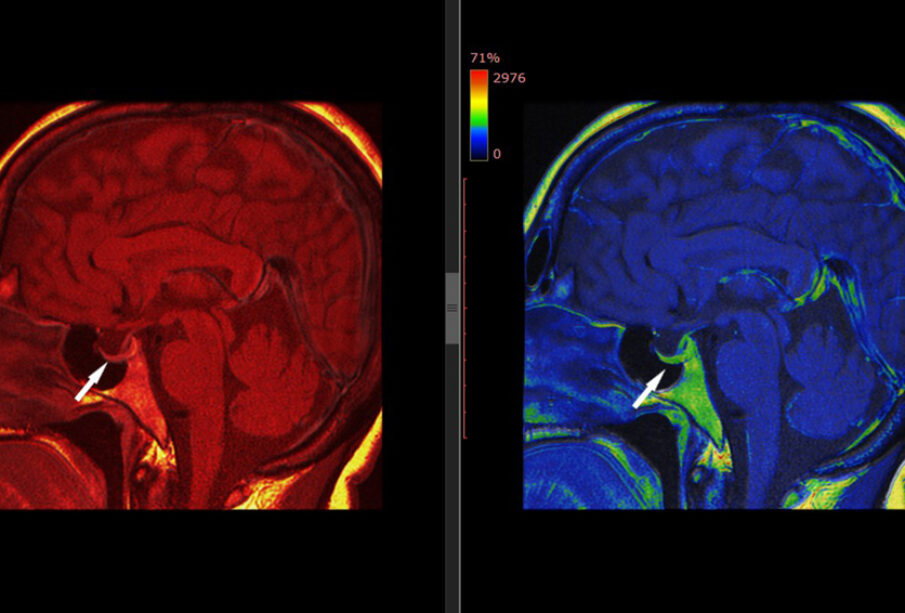

Didėjant hipofizės adenomai, neretai spaudžiamas regos nervas arba vieta, kur susikryžiuoja abiejų akių regos nervai – vadinamasis regos nervų kryžmė. Regos nervas perduoda regimąją informaciją iš akies į smegenis, o kryžmėje susikerta signalai iš abiejų akių. Spaudžiant šias struktūras, dažnai silpnėja regėjimas, ypač periferinis matymas. Kai netenkama išorinio matymo lauko (šoninio regėjimo), ši būklė vadinama bitemporaline hemianopsija.

Kaip nustatoma hipofizės adenoma

Pasitaiko, kad pirmieji ligą pastebi akių gydytojai, nes navikas dažnai pradeda reikštis būtent regėjimo pakitimais. Siekiant įvertinti regos funkciją, atliekamas kompiuterinis regos lauko tyrimas. Taip pat labai svarbi išsami asmens sveikatos istorija, nes hipofizės navikai gali sukelti hormonų pokyčius. Diagnozei patikslinti gali būti atliekami kraujo ir šlapimo tyrimai, bei galvos magnetinio rezonanso (MRT) tyrimas.